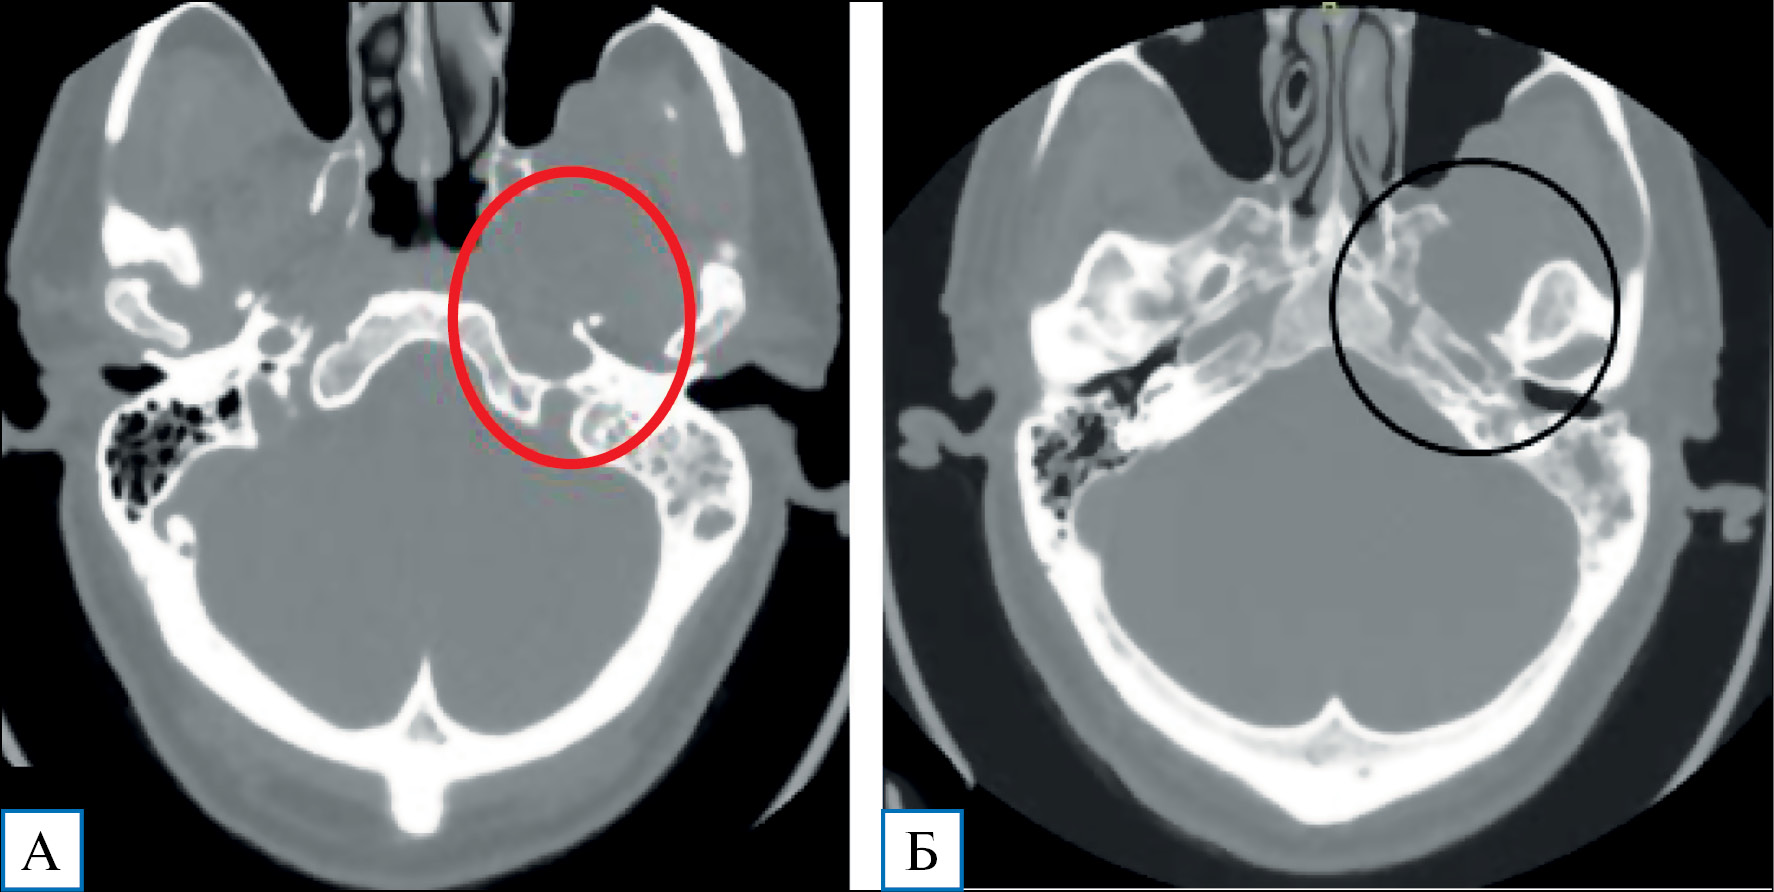

Невринома вызывает компрессию ножек мозга, моста, корешков VII и VIII нервов, а также деструкцию височной кости с развитием петрозита и мастоидита (рис. 2).

Рис. 2. Пациент М. с невриномой тройничного нерва, 60 лет: компьютерная томография головного мозга с контрастным усилением

Примечание. На КТ-изображениях в костном режиме определяются деструкция пирамиды височной кости в проекции меккелевой полости, рваного отверстия (А), а также деструкция основания средней черепной ямки с расширением овального и круглого отверстия (Б).